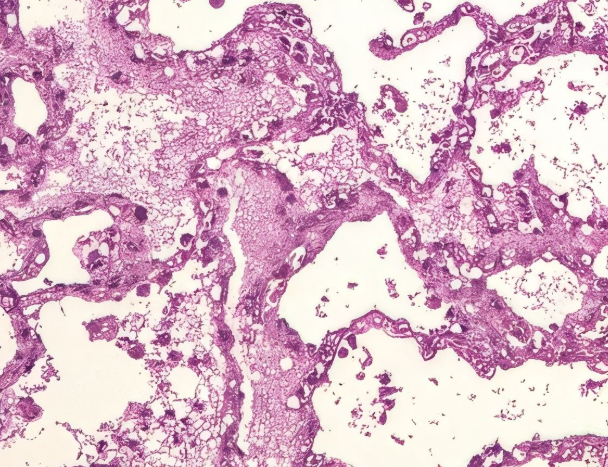

В рамках данного исследования в качестве источника реальных данных были использованы микроскопические изображения легких, предоставленные Бюро судебно-медицинской экспертизы г. Байконур (рисунки 2, 3). Визуальный анализ подтверждает, что предложенный автоэнкодер лучше сохраняет границы объектов и текстурные структуры по сравнению с традиционными фильтрами.

На рисунках 2 и 3 изображены микроскопические снимки легких до и после фильтрации.

Рисунок 3 - Изображение после фильтрации

Однако на практике получаемые изображения часто характеризуются наличием различных искажений — шумов, размытости, пониженного контраста и других артефактов, обусловленных как техническими ограничениями микроскопического оборудования, так и условиями съёмки. Эти факторы затрудняют визуальную интерпретацию и автоматизированную обработку изображений, снижая точность диагностических и экспертных выводов.